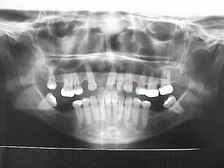

| RADIOGRAFIA PANORÂMICA INICIAL |

| |

Articulação dentária, planejamento e execução realizados pelo Dr. Amilcar Fernandes da Silva Neto